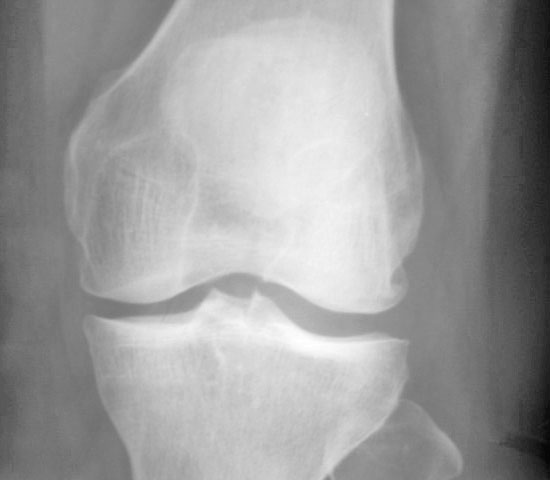

女.50.膝关节疼痛伴伸直困难.请会诊

退变,骨质增生,关节腔游离体,后方二个箭头似为滑膜钙化。

考虑双侧膝关陈退行性骨关节病/。  滑膜钙化。

膝关节退行性骨关节病并关节游离体。

退行性骨关节病;肯定不是游离体,正位与股骨外侧髁重叠,侧位在膝关节后方,为腓肠小骨(腓肠肌外侧头肌腱内常见的一枚子骨)。

右膝关节呈退行性改变,关节囊后方多个游离体,符合滑膜骨软骨瘤病。髌韧带增厚,边缘模糊,髌下脂肪垫密度增高,符合滑膜炎。